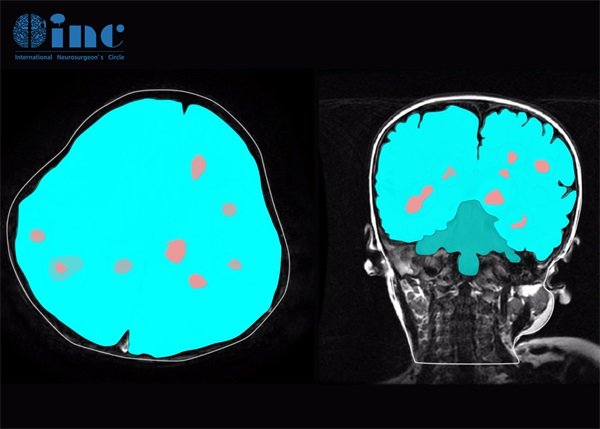

在手术前,影像学检查如MRI或CT会帮助医生了解血管瘤的确切位置,判断其大小及与周围组织的关系。这种信息对手术方案的制定尤为重要,才能大程度上降低手术风险。

2023年4月9日,23岁的大学生斌斌因为功能区——半卵圆中心海绵状血管瘤接受了INC巴特朗菲教授的顺利全切手术。骑自行车、打篮球、正常学习上课……凭借巴教授高超的手术技术,术后的斌斌早已恢复正常生活重回大学校园,而术后INC也一直对斌斌进行着常规随访。

术后核磁共振检查结果好,病灶完全切除,周围区域也很干净。因此,手术目标已经完全达到。下一次核磁共振检查应在一年后,即2025年春季进行。

2024年4月,我们也收到了巴教授发来的随访邮件,在查看了斌斌术后一年核磁影像后,巴教授回复目前斌斌的情况好,肿瘤全切一年后没有复发。